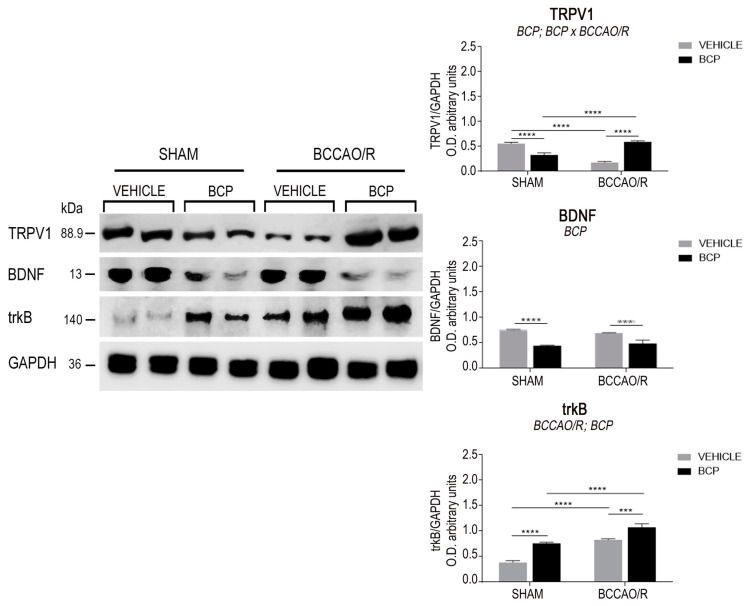

The effects of the BCCAO/R without and with preventive administration of BCP on the relative levels of TRPV1, BDNF, trkB, GFAP, and Iba1 proteins are summarized in Table 1 and shown in Figure 1 and Figure 2. Statistical analysis of O.D. values of the immunostained protein bands performed by two-way ANOVA (main factors BCCAO/R and BCP) (Table 1) revealed that both the BCCAO/R-induced molecular changes and the effect of the BCP pre-treatment occurred in the frontal cortex, whereas no statistically significant differences were evident in the temporal-occipital cortex.

2.1.1. The TRPV1 Protein Levels

The antibody against TRPV1 labeled a protein band with a relative mw of 89.9 kDa (Figure 1 Left), consistent with the reported mw of the receptor monomeric form [ref. 55]. Assessment of the TRPV1 densitometric values by a two-way ANOVA (Table 1) revealed an effect of BCP (p = 0.0072) and a significant BCP × BCCAO/R interaction (p < 0.0001). Pair-wise contrasts further showed that, in the vehicle-treated animals, a statistically significant decrease of TRPV1 relative protein levels, amounting to −201%, occurred in BCCAO/R vs. sham-operated rats (p < 0.0001). After the BCP pre-treatment, relative levels of the TRPV1 decreased in the sham-operated (−62%; p < 0.0001) while increased in the BCCAO/R rat group (+69%; p < 0.0001) as compared to the vehicle-treated rats; finally, a statistically significant increase of TRPV1 relative levels occurred in BCCAO/R-rats as compared to sham-operated ones (+42%; p < 0.0001).

2.1.2. The BDNF Protein Levels

The antibody against BDNF labeled a protein band with a relative mw of about 13 kDa (Figure 1), according to the expected mw of the monomeric form of the protein [ref. 56,ref. 57]. Assessment of the BDNF densitometric values by a two-way ANOVA (Table 1) revealed an effect of BCP (p < 0.0001). The slight reduction of BDNF relative levels in the BCCAO/R rats (0.7592 ± 0.01 in sham rats vs. 0.6936 ± 0.004 in BCCAO/R rats) is consistent with previously published data [ref. 20]. Such a decrease was highly statistically significant with an unpaired t-test analysis (p < 0.0001), however, it did not reach the statistical significance with the pair-wise contrasts run after the ANOVA. Pair-wise contrasts instead showed that, after the BCP pre-treatment, the relative levels of BDNF protein were decreased in both sham-operated (−71%; p < 0.0001) and BCCAO/R rats (−42%; p = 0.0001) as compared to the vehicle-treated rats.

2.1.3. The trkB Protein Levels

The anti-trkB antibody, raised against the full-length isoform of the receptor protein, recognized a protein band with a relative mw of about 140 kDa (Figure 1), consistent with the reported mw of the receptor protein [ref. 57,ref. 58]. Assessment of the trkB densitometric values by a two-way ANOVA (Table 1) showed effects of the BCCAO/R (p < 0.0001) and of the BCP pre-treatment (p < 0.0001). Pair-wise contrasts revealed that, as a general rule, the BCP-treatment induced an increase of trkB relative levels amounting to about 97% (p = 0.0024) and 33% (p = 0.0028) in the sham-operated and BCCAO/R rats, respectively, vs. the vehicle-treated ones. In particular, in vehicle-treated animals, the trkB protein relative levels increased by 119% in BCCAO/R (p < 0.0001) vs. the sham-operated rats, while in the BCP-treated rats increased by 47% (p = 0.0002) in the BCCAO/R vs. the sham-operated.